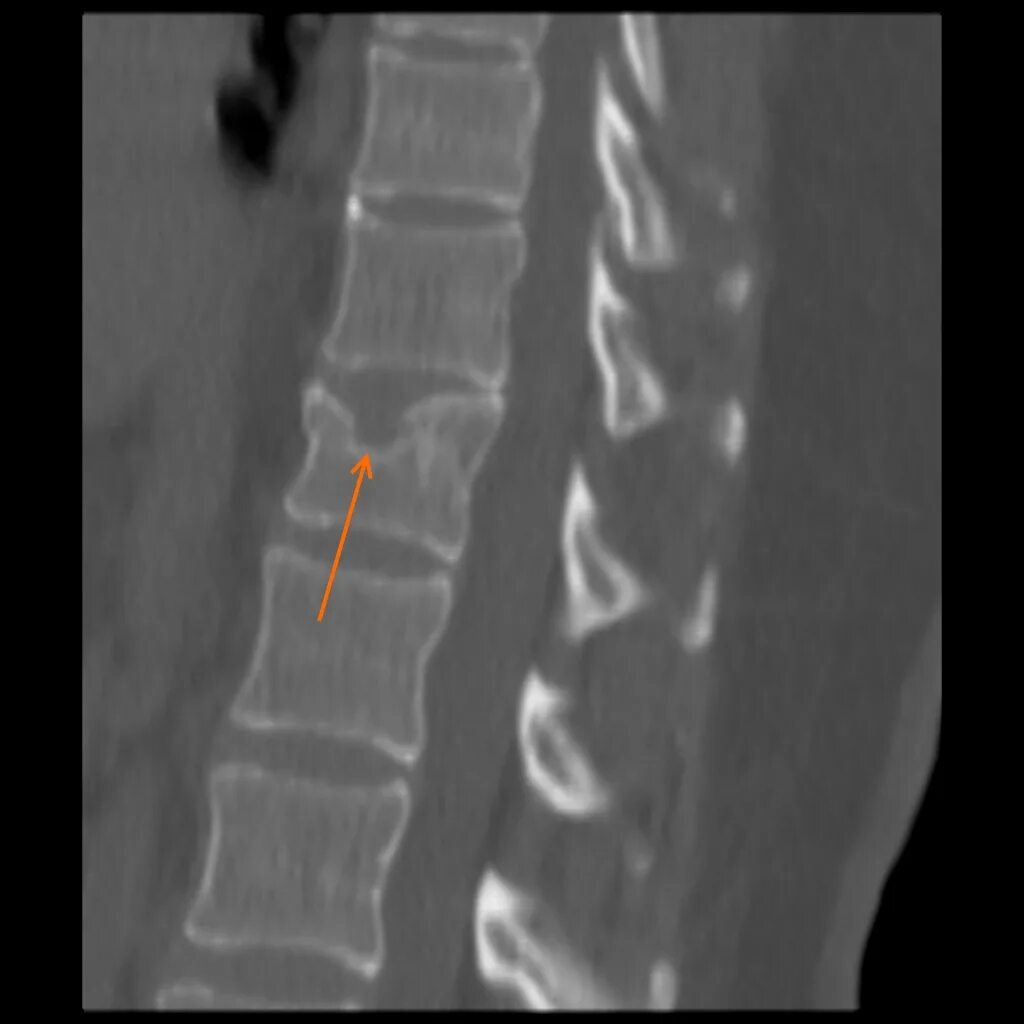

Протрузии шморля